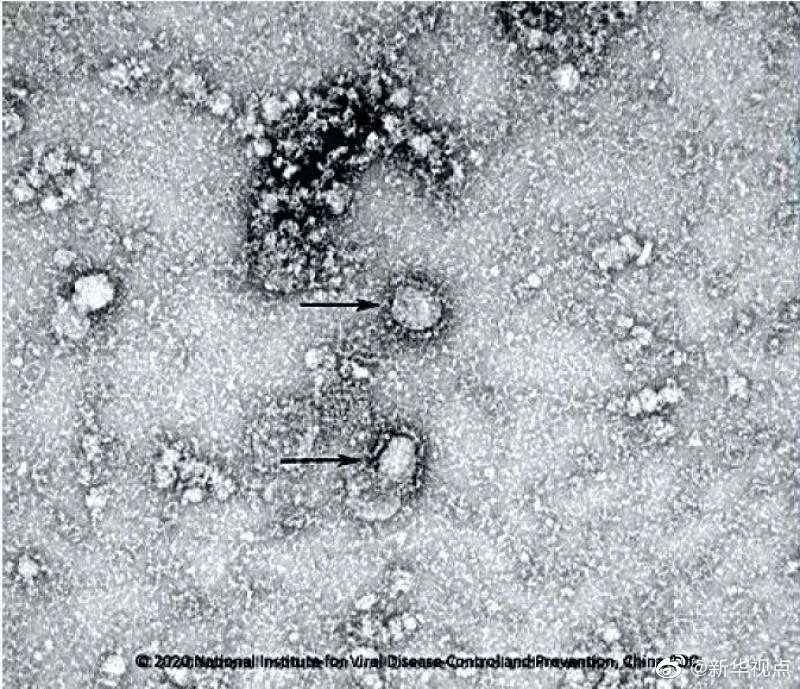

國家病原微生物資源庫于2020年1月24日發(fā)布了由中國疾病預防控制中心病毒病預防控制所成功分離的我國第一株病毒毒種信息及其電鏡照片、新型冠狀病毒核酸檢測引物和探針序列等國內(nèi)首次發(fā)布的重要權(quán)威信息,并提供共享服務??床《尽罢嫒荨薄ㄓ浾咛飼院健⑼醣枺?/p>

好消息!中國疾控中心成功分離我國首株新型冠狀病毒毒種,它長這樣!-新華網(wǎng)